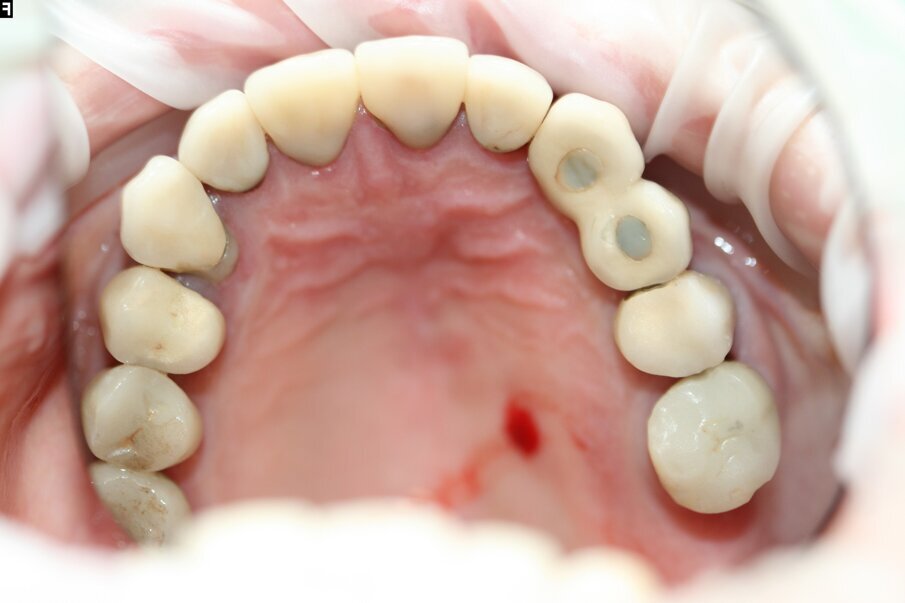

A 76-year-old female patient visited our clinic owing to pain in the left maxilla. She had a fistula in the buccal gingiva between tooth #25 and position #24. There were implants in positions #24 and 23. Tooth #25 already had a crown. The tooth had been affected by secondary caries earlier and had been repaired. A periapical radiograph showed an active inflammatory process in progress from the endodontically treated tooth that greatly worsened the prognosis and could have adversely affected the implants. The prognosis was therefore considered poor and we decided to extract the tooth.

Fig. 3: Maxillary arch before treatment.